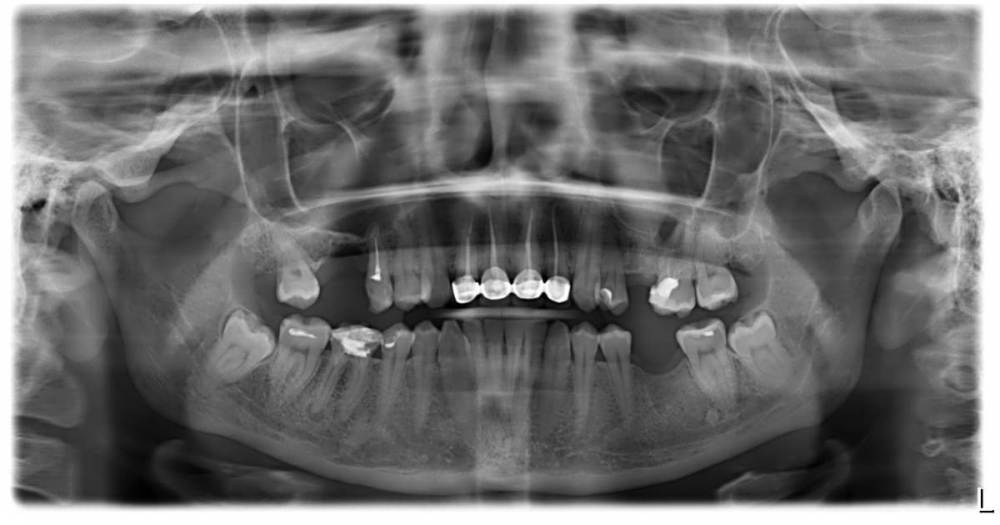

АйгульШ Опубликовано 12 ноября, 2021 Поделиться Опубликовано 12 ноября, 2021 Здравствуйте! Подскажите пожалуйста, можно ли по моему снимку определить все ли нормально с зубами под коронками? Нужно ли менять? И буду благодарна за информацию какие зубы нужно срочно лечить, а какие ещё могут подождать Ссылка на комментарий

Notherbrick Опубликовано 13 ноября, 2021 Поделиться Опубликовано 13 ноября, 2021 Конкретно этот снимок даёт нам понять, что зубы под коронками требуют ревизии и с ними не все нормально. 15, 26, 46 требуют внимания 100%. И необходимо вернуть на место отсутствующие три зуба (16, 25, 36) Зубы мудрости желательно планово удалить. Это что касается предоставленного снимка. Более основательно составить план можно после очного осмотра и дополнительного обследования. 1 Ссылка на комментарий